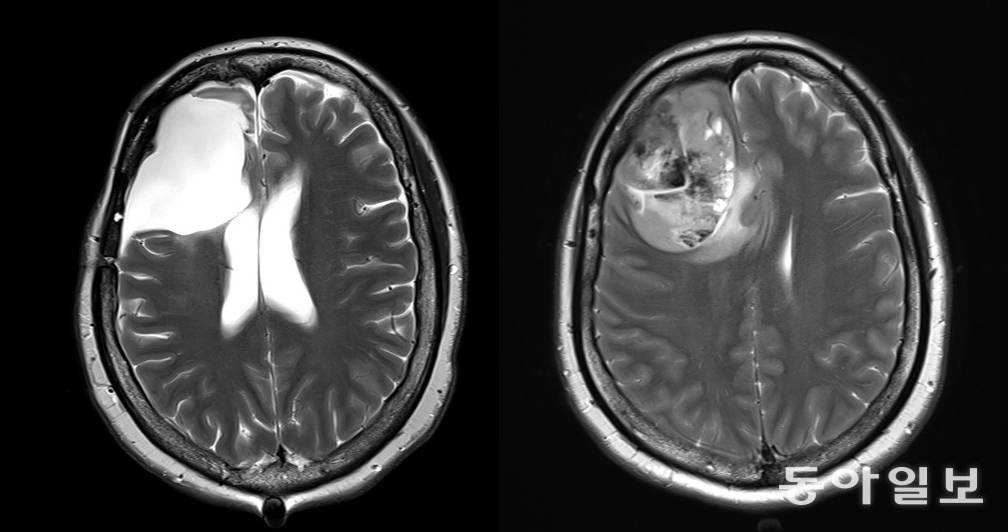

뇌종양(교모세포종)을 앓는 환자의 뇌 MRI 사진(왼쪽)과 뇌종양(교모세포증) 환자의 종양을 제거한 후 뇌 MRI 사진(오른쪽). 동아일보 DB